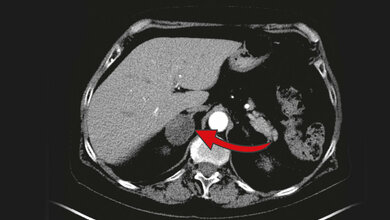

Doch auch bei der Diagnostik geht es mit Riesenschritten voran. Neben den neuen Möglichkeiten in der Bildgebung ist hier beispielsweise Liquid Biopsy ein Schlagwort. Die Nukleinsäureanalytik zum Nachweis von Tumorzellen und Tumor-DNA sorgt für Furore.